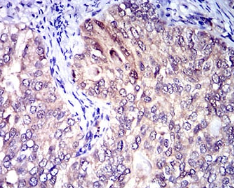

IHC    1/200 - 1/1000